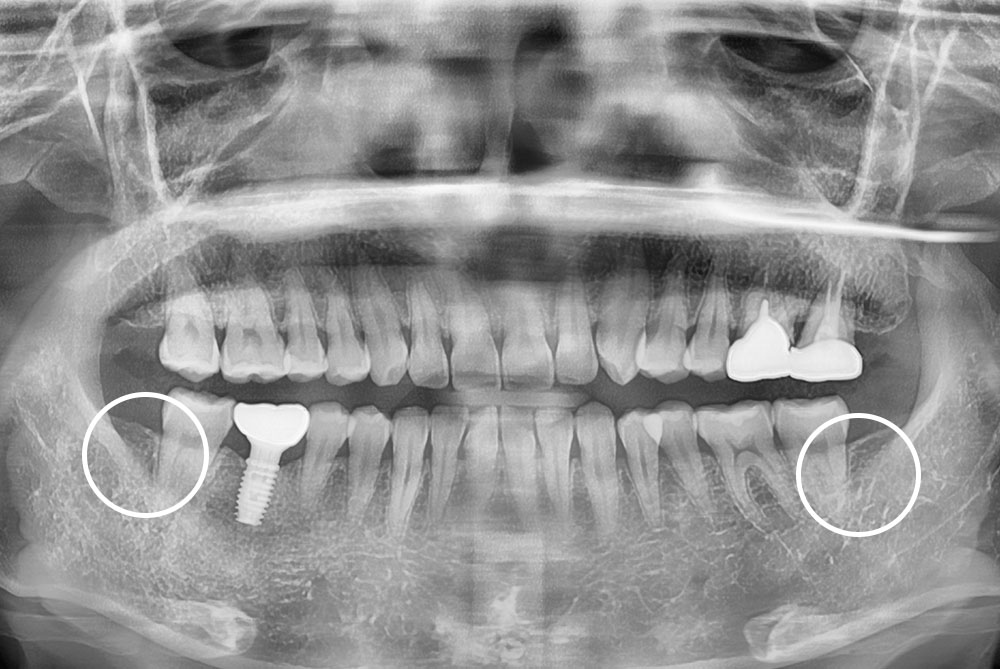

[사랑니] 매복 사랑니 발치

치료전 : 2019-02-23

세종치과는 구강악안면외과학 박사이신 원장님이 발치하는 치과입니다.